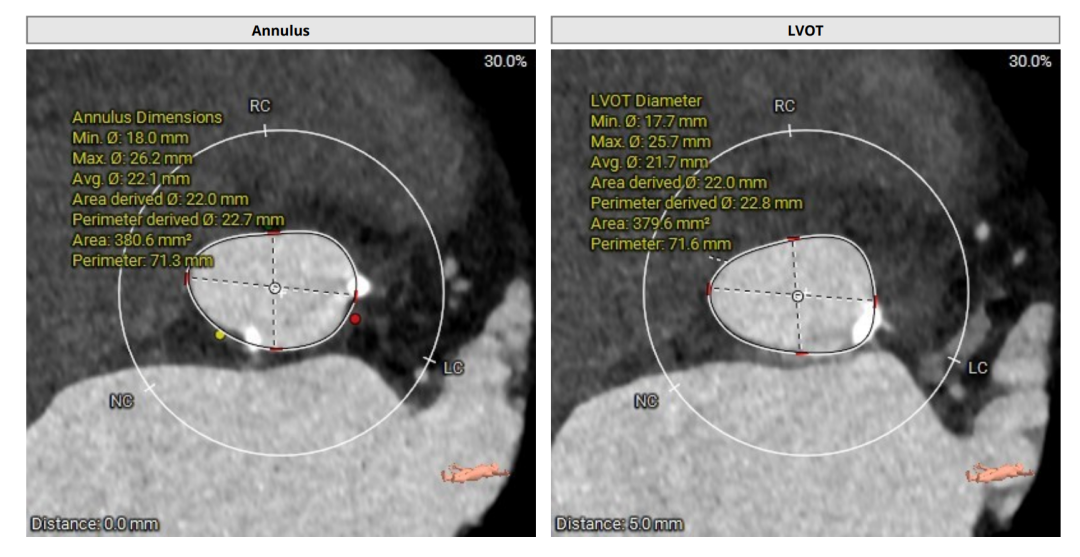

术前评估

术前CT(上下滑动查看更多图片)